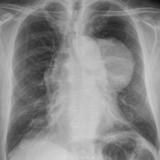

Case 8a Thymoma PA

Date: 03/27/2009

Views: 9457